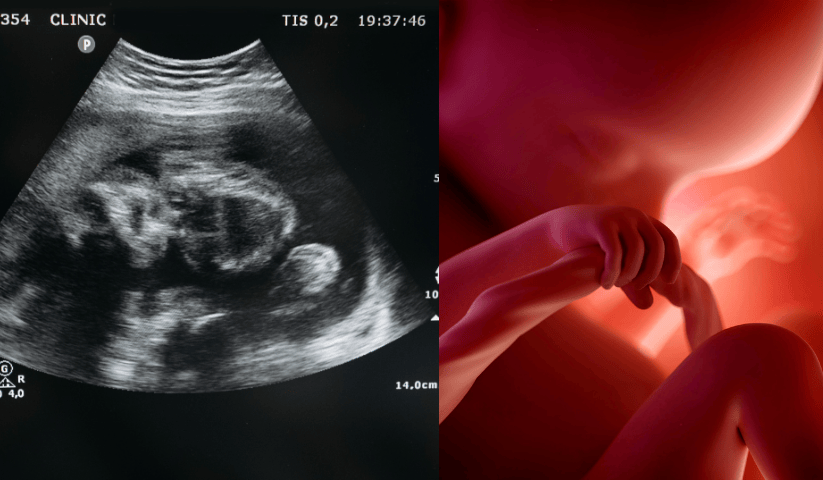

28 Aprile 2025Durante la gravidanza, il corpo femminile va incontro a profondi cambiamenti, pensati per sostenere non solo la salute della mamma, ma anche la crescita e lo sviluppo del feto. Tra queste trasformazioni, una delle più comuni – ma anche delle più sottovalutate – è una riduzione dei livelli di ferro nell’organismo. L’anemia in gravidanza è tutt’altro che rara, ma ciò non significa che possa essere sottovalutata, anzi: è importante capire cosa comporta, quando preoccuparsi e soprattutto come intervenire in modo efficace e sicuro.

Cosa succede al feto se la mamma è anemica?

Senza voler fare allarmismo, una carenza di ferro importante e prolungata può compromettere l’ossigenazione dei tessuti fetali, aumentando i rischi di:

- Ritardo di crescita intrauterina

- Parto pretermine

- Basso peso alla nascita

- Alterazioni nello sviluppo neurologico

Per questo motivo, anche una lieve anemia non va sottovalutata, perché potrebbe essere il primo segnale di un’evoluzione da monitorare: il ferro non è solo importante per la salute materna, ma anche per quella del bambino.